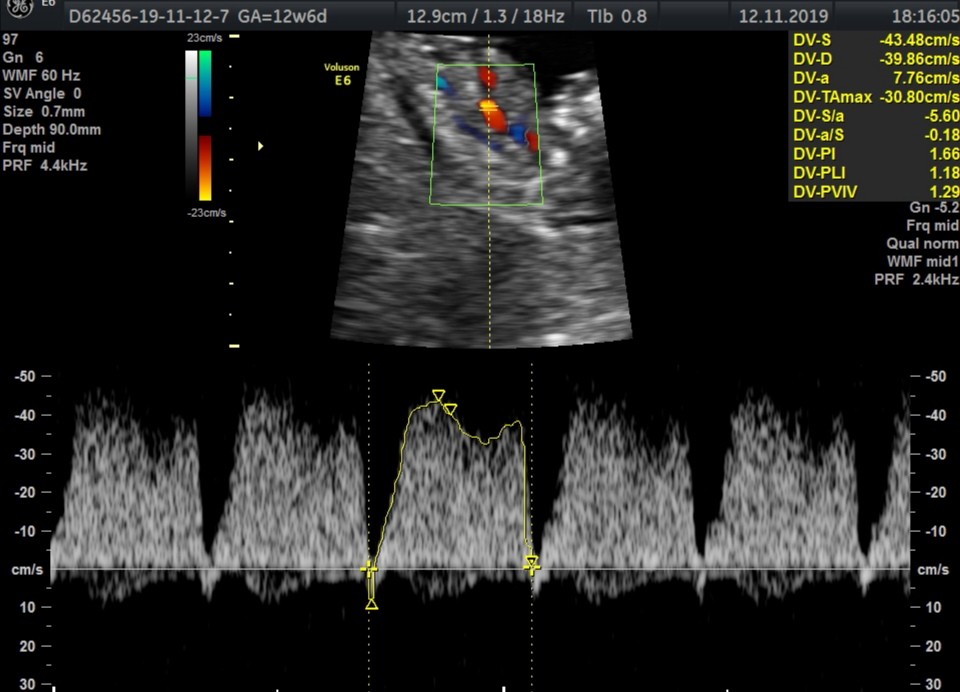

Czy u tych dziewczyn, które są już po tym badaniu, lekarz komentował może parametr DV, czyli prawidłowość przepływu w przewodzie żylnym? U mnie wyszła zwrotna 'fala a', co nie jest do końca prawidłowym obrazem. Ponadto dziecko takie fikołki kręciło, że trudno było uwidocznić kość nosową, ale pani doktor stwierdziła, że NAJPRAWDOPODOBNIEJ (ech...) ją widzi. Pozostałe parametry usg w normie.

Czy u którejś z Was w parametrze DV pojawiła się zwrotna 'fala a'?

Dla porównania załączam zdjęcie.

Nt prawidłowe, 1,40. Lekarz, który przeprowadzał badanie (z certyfikatem FMF) zaznaczył, że ta 'niepoprawność' DV u wielu dzieci naprawia się samoczynnie w kolejnych tygodniach, a więcej będzie widać również na badaniach polowkowych (dopiero w styczniu) - wowczas ewentualne zalecenie wykonania echa serca. Na chwilę obecną mamy czekać na wyniki pappa.